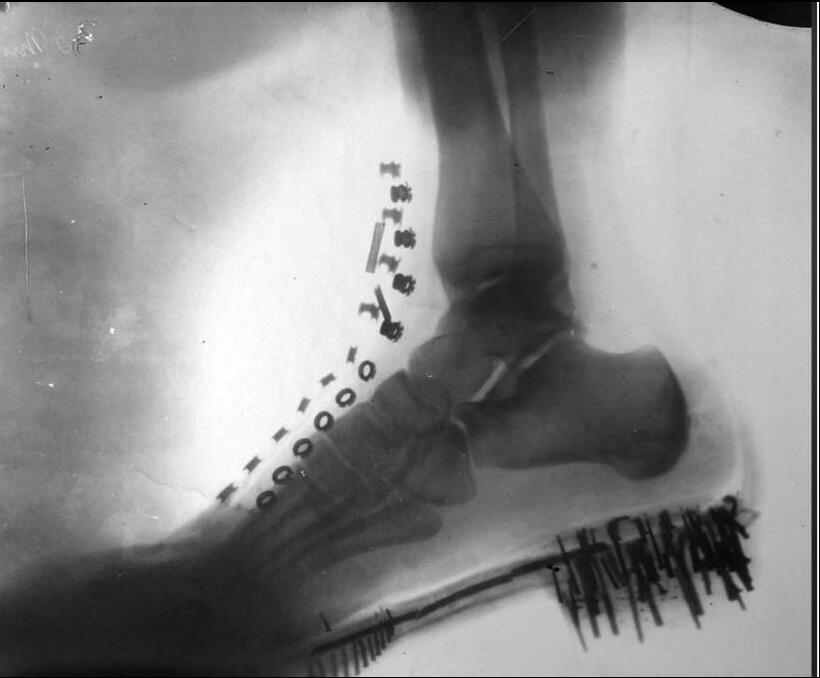

ŠTA SE KRIJE IZA RENDGENSKOG SNIMKA TESLINE NOGE?! Pojavila se fotografija iz 1896! Aparat SAM napravio, rezultat je ZAPANJUJUĆI!

Printscreen/Facebook/Nikola Tesla Serbian Genius